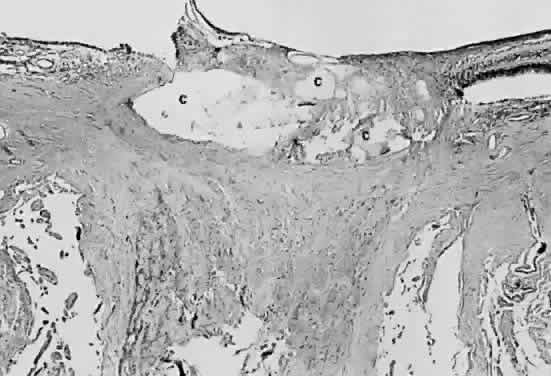

Structures in the fundus may calcify, but the resultant white changes typical of calcium may be difficult to discern ophthalmoscopically because of the location of the calcium, viz., drusen of the optic nerve head. These calcific concretions are buried within the substance of the optic nerve head, usually anterior to the lamina scleralis (Fig. 28). They are covered by axonal and glial tissue together with the vascular supply of the nerve head. They are recognizable because of distortions in the shape of the disc, not the characteristic white color of the calcified lesion (Fig. 29). Drusen of the optic nerve head must not be confused clinically with papilledema (Figs. 30 and 31), with so-called “giant drusen,” which are glial hamartomata, or with drusen of the pigment epithelium, which are deposits of basement membrane material between the pigment epithelium and Bruch's membrane.

Fig. 28. Photomicrograph of drusen of the optic nerve head. Calcium (c) is deposited in the nerve anterior to the lamina scleralis. The optic nerve in this case is markedly atrophic. The retina to the left of the nerve is artifactually detached and missing from the plane of the section.